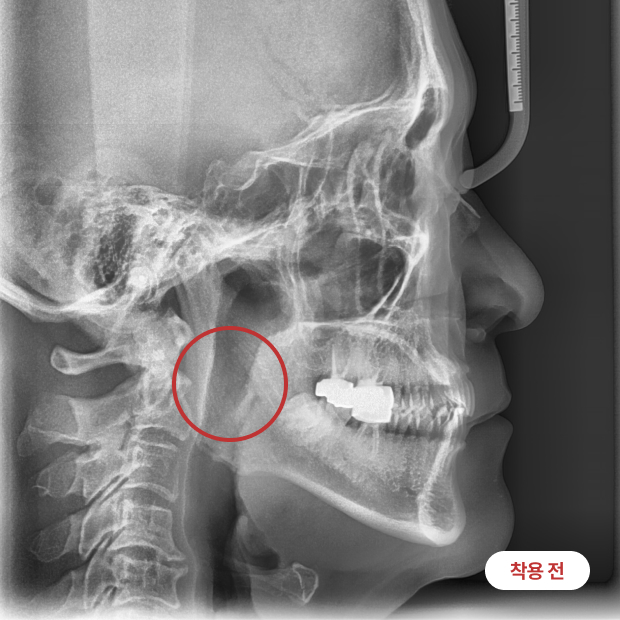

착용 전/후

넓어진 기도를

확인해보세요!

장치를 착용하면서 근기능 훈련을 함께하면 구호흡을 방지하고 비호흡을 유도하며,

아래턱이 앞으로 나와 기도가 넓어지는 효과를 경험할 수 있습니다.

이로 인해 코골이와 수면무호흡의 정도를 줄일 수 있습니다.